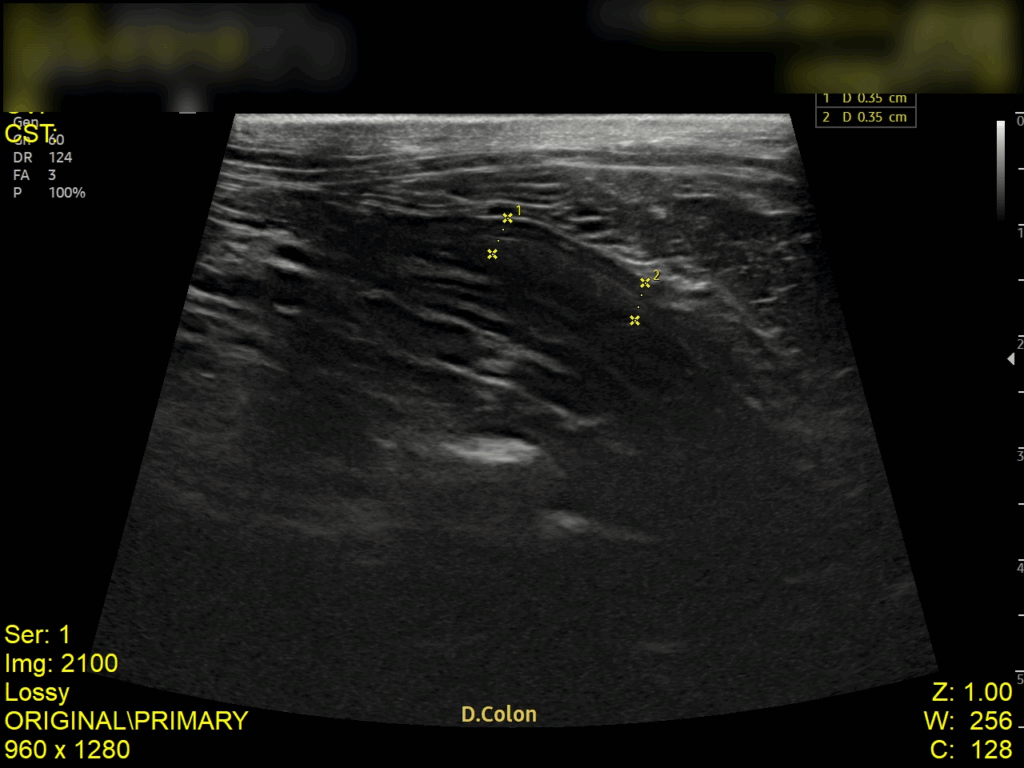

복부 초음파 검사 결과

초음파 검사 결과, 복강 내 림프절이 비대된 모습이 확인되었고, 장벽 두께가 정상보다 두꺼워진 것을 확인되었습니다. 이는 장 내 염증 반응이나 감염성 원인에 의해 장벽이 자극을 받고 있음을 의미합니다.